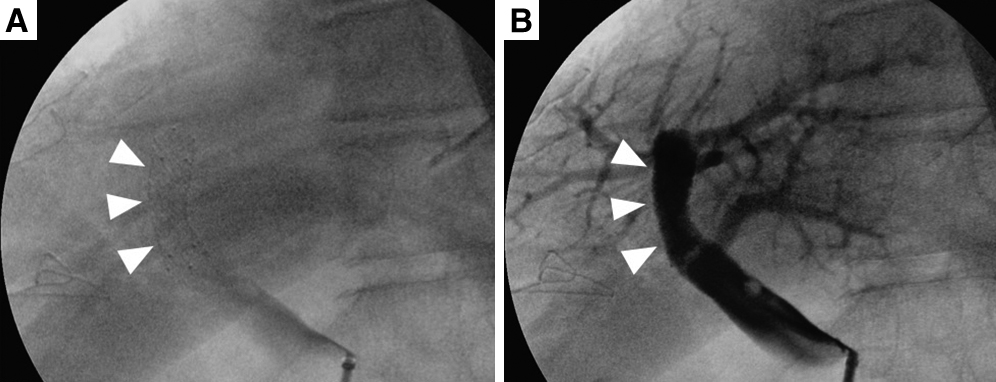

手術所見:右季肋下切開で開腹した.腹水および明らかな遠隔転移は認められなかった.肝円索および肝鎌状間膜を切離して術野を広げ,前方アプローチにより肝右葉切除を行った.肝門部グリソンは個別処理を行い,門脈右前区域枝・右後区域枝は,門脈本幹から十分に離れた位置で門脈左枝が狭窄しないように注意してそれぞれを切断した.具体的には,分岐部から約15 mmのそれぞれの門脈を切断し,断端を連続縫合閉鎖した.肝左葉の脱転は行わなかった.標本摘出後に術中超音波検査を施行したところ,肝左葉の門脈血流が確認されなかった.回結腸静脈から7 Frのシースを留置し門脈造影を行うと,尾状葉枝のみが造影され門脈左枝より末梢は造影されなかった(Fig. 3A).肝右葉のあったスペースに傾いている残肝を左側に戻すと門脈血流の再開が確認されたため,血栓による血流障害ではなく肝左葉がこのスペースへ傾くことに伴う門脈左枝の捻転が原因と考えられた.しかし,残肝を左側に戻したときの再開門脈血流はその位置により変化し非常に不安定であったため,このまま肝円索を腹壁に固定することで肝左葉を固定する方法では不十分と判断した(Fig. 3B).また,門脈の切除・再建による捻転の解消も検討したが,この段階で門脈本幹周囲の剥離は十分でなく,また門脈が余剰とはいえない所見であったため,切除・再建は容易でなく,また確実性は少ないと判断した.以上より,放射線科医師の協力のもと門脈ステント留置の方針とした.先に留置したシースより,門脈臍部から門脈本幹にかけてステントを留置した(Fig. 4).ステントはEpic Vascular self-expanding stent system;10 mm径×40 mm長(Boston Scientific Co.)を使用した.門脈圧格差は計測しなかった.ステント留置後の門脈造影では門脈左枝の血流は十分に再開し,超音波検査でも門脈血流を確認することができた.術後に門脈血栓予防としてヘパリンを注入するため上腸間膜静脈内にカテーテルを留置し,手術を終了した.

(A) A self-expandable metallic stent was inserted to improve the torsion of the left branch of the portal vein. (B) Portography showed that blood flow in the left branch of the portal vein was fully resumed after stent placement (arrowheads).